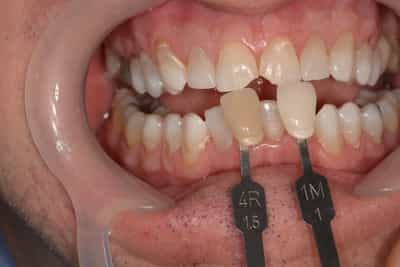

Les composites stratifiés

Lorsqu’un délabrement survient sur une dent antérieure (visible, où l’esthétique est une priorité), et que l’indication n’est ni une facette, ni une couronne, nous vous proposons de réaliser une restauration par un composite stratifié. Il s’agit de reconstituer la partie manquante de la dent, en respectant les différentes entités de la dent. Nous monterons différentes masses de dentine, d’émail, les particularités de la dent, en respectant la carte d’identité de la dent (établie selon une analyse et des relevés morphologique de la dent, cartographique de la couleur, cartographique de l’émail et de la dentine, topographique (état de surface)).